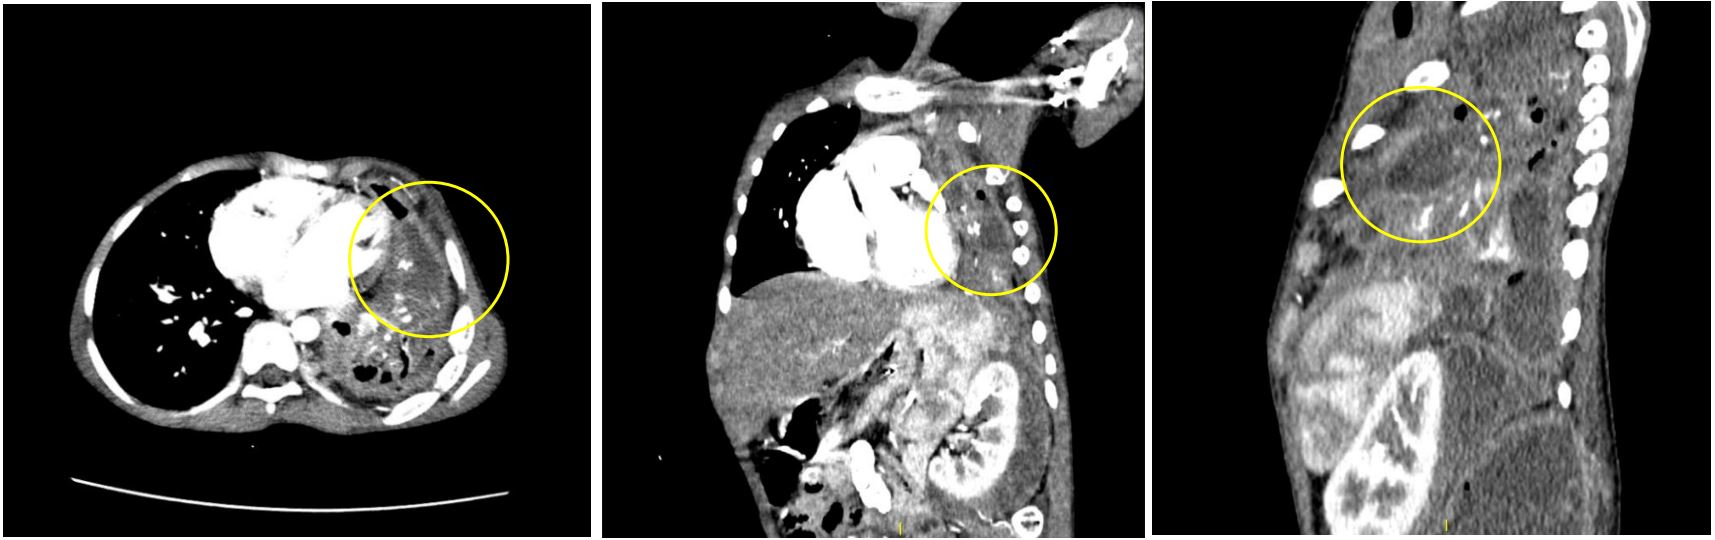

Figure 4: Contrast-enhanced CT showing extent of the intra-thoracic involvement of the abdominal abscesses (yellow circles).

Figure 5: Contrast-enhanced CT showing axial (A), Coronal (B), And sagittal (C) Views depicting a hypodense collection within a thick-enhancing pleura in the left lower hemithorax (yellow circle), Compatible with empyema thoracis.

We present a case of P.M. An 11-year-old who initially presented with a three-week history of cough, Intermittent fever, and dyspnea. The initial diagnosis of left congenital diaphragmatic hernia was suspected from the chest radiograph and ultrasound in another institution as an opacified left hemithorax and bowel loops within the left thoracic cavity were found, respectively. The patient was subsequently referred to our institution where chest radiograph (Figure 1), chest ultrasound (Figure 2) and contrast-enhanced CT scan of the chest and upper abdomen (Figure 3-7) were done showing left perinephric and left psoas abscesses with intra-thoracic extension, probably through a left diaphragmatic defect, forming empyema thoracis and empyema necessitans. Culture of abscess fluid yielded no bacterial growth but GenExpert test was positive for M. tuberculosis.